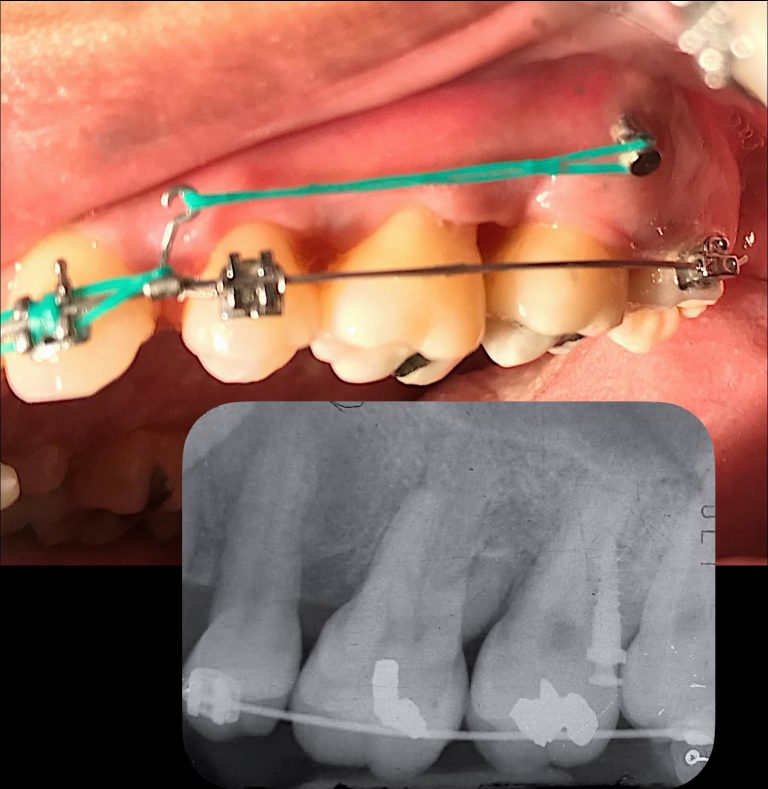

Wilcko & Wilcko แนะนำว่าไม่ควรให้แรงจัดฟันช้ากว่า2สัปดาห์หลังผ่าตัด โดยรายงานห้วงเวลาwindow of rapid of tooth movementเพียง4-6เดือนหลังผ่าตัดเท่านั้น จึงทำให้บางprotocolมีคำแนะนำให้มีการactivate orthodontic forceถี่ขึ้นเป็นเดือนละ2ครั้ง

ซึ่งในช่วง20ที่ผ่านมาก็มีการmodified technique PAOOออกมาอย่างหลากหลายตราบใดที่มนุษย์เรายังไม่หยุดพัฒนาความรู้และเทคโนโลยี ไม่ว่าจะdesign flapเปลี่ยนไปเป็นtunnelบ้าง ใช้กล้องmicroscopeร่วมกับการผ่าตัดบ้าง นำเอาเครื่องมือpiezo surgeryมาใช้บ้าง เป็นต้น โดยต่างก็รายงานถึงข้อดีของเทคนิคนั้นๆ รวมทั้งก็สามารถทำให้การเคลื่อนฟันเกิดได้เร็วขึ้นเช่นกัน

-PAOOอาจเข้ามามีประโยชน์ในกรณีที่orthodontistพบจุดติดที่ไม่สามารถเคลื่อนฟันผ่านสันridgeที่บางได้จริงๆจากการพยายามแล้ว (เพราะPAOOให้ผลทำให้สันridgeหนาขึ้นด้วย)